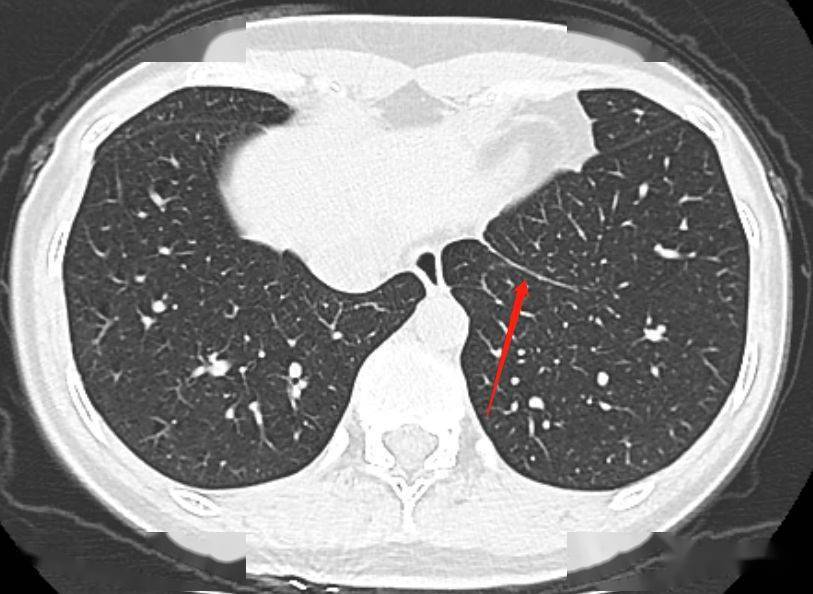

胸部ct上的"肺韧带",别再报纤维条索了

胸部ct天天见,却不认识的结构:肺韧带

十六,左,右肺韧带层面(断层十六)关键结构:左,右肺韧带及位于后

肺位于胸腔内,纵隔两侧,左右各一,借肺根和肺韧带与纵隔相连.

是人胚胎发育过程中的胸膜残存部分.左,右肺韧带的显示率分别为60-70